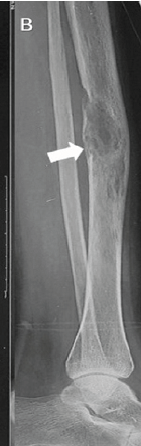

A Rare Case of Intraosseous Venous Malformation of Tibia in a Young Female – A Diagnostic Dilemma

Divesh Jalan , Puneet Garg , Rohit Prasad , Geetika Khanna , Dharmendra K Singh

………………………………p.265-269